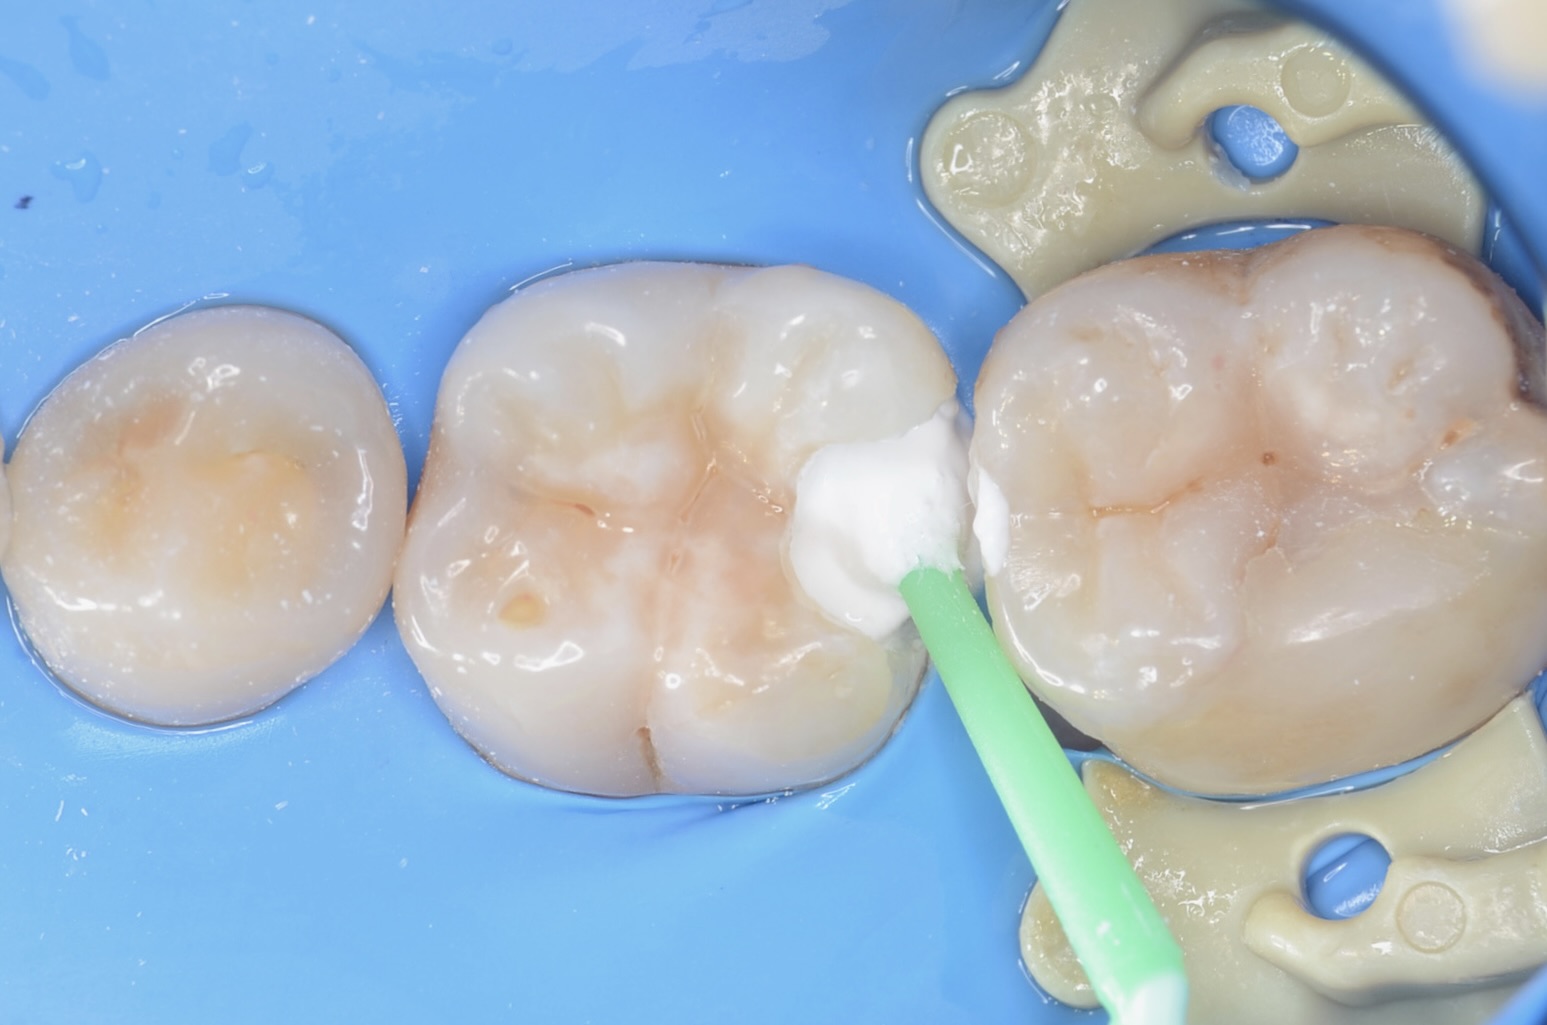

レジン充填

青色のテフロンテープを紐状にしたものを歯肉溝に挿入しました。レジンが、ラバーダムに触れないようにするためです。一気にレジンを充填して硬化させるとレジンの重合収縮によりレジンが、歯から引き剥がされる力がはららいてしまうので。少量づつレジンを充填硬化させます。 -

3Dプリンターテクニック

フロワブルレジンを用いて、その表面張力を利用して滑らかで段差のないレジン充填を実現させます。 セパレーターで歯間離開させながら光を当てながらレジンを硬化させる3Dプリンターテクニックを用いて治療しました。 -

ダイレクトボンディング終了

咬合面にはペースト状のレジンで、形態を作りました。天然歯の自然な形態を模倣してレジンを充填しました。 -